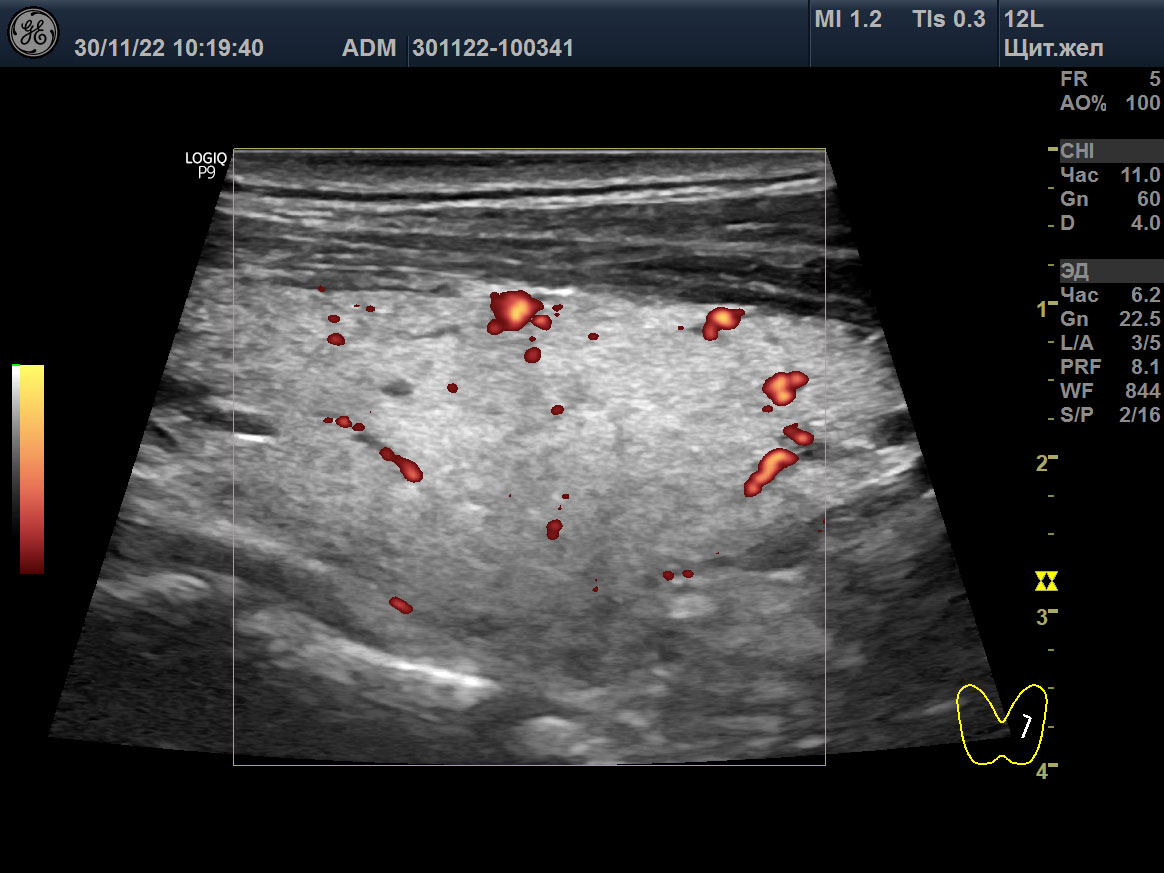

15 мая 2018 ультразвуковое исследование (УЗИ) щитовидной железы выявило зоб 3 степени (объём 45 мл; 23,6D + 21,4S), признаки умеренного отёка стромы (гомогенная гипоэхогенность паренхимы), значительное усиление интенсивности кровотока, систолическую пиковую скорость (SPV) кровотока в системе верхних щитовидных артериях (STA) 123 cm/sec справа и 160 cm/sec слева (рисунок: A, B, C).

A

B

C

D

E

F

Изображения щитовидной железы пациента в режиме Допплера. A, B, C ― до лечения (15 мая 2018), и D, E, F после лечения (23 августа 2021). A, D ― поперечная проекция левой доли. B, E ― продольная проекция левой доли. C, F ― SPV STA слева.

Вместе с тем, в августе 2021, при нормальном гормональном обмене и АТ-рТТГ 0,3 Ед/л (<1,5), объём щитовидной железы остался прежним (30,4 мл), у дорсального края в обеих долях сохранялись некоторые признаки отёка стромы, интенсивность кровотока с двух сторон в очень малой мере была усилена, улучшилась SPV STA – 27 cm/sec справа и 39 cm/sec слева (таблица 2; рисунок: D, E, F). В декабре 2022 ультразвук показал подобные признаки с незначительным улучшением: объем щитовидной 24 мл и преобладание изоэхогенной паренхимы.